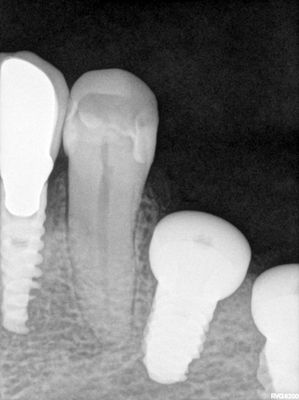

large amount of bone loss at time of exo 36/37 done 2 months ago. Good healing of bone except for small socket area at 36 region. buccal bone lower than palatal about 1mm, decided to place tissue level implants opposed to grafting, gaining back height is unlikely, difficult access case with large tongue. Implants placed with 36 about 1.5mm buccal exposed, 37, .5mm mesial exposed, healing abutments palced grafted all sites with sticky bone followed by collagen membrane soaked in prf fluid, 2 holes cut for implants. additonal fibrin membrance placed on buccal prior to suturing.